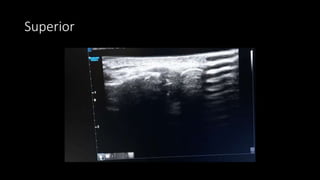

Superior scanning protocol

• Transducer along long axis of the

clavicle, move laterally until to

profile the joint space

• Overlying hypoechoic joint

capsule

• Fibrocartilagenous disc seen as

linear hyperechoic structure in

the center of the joint